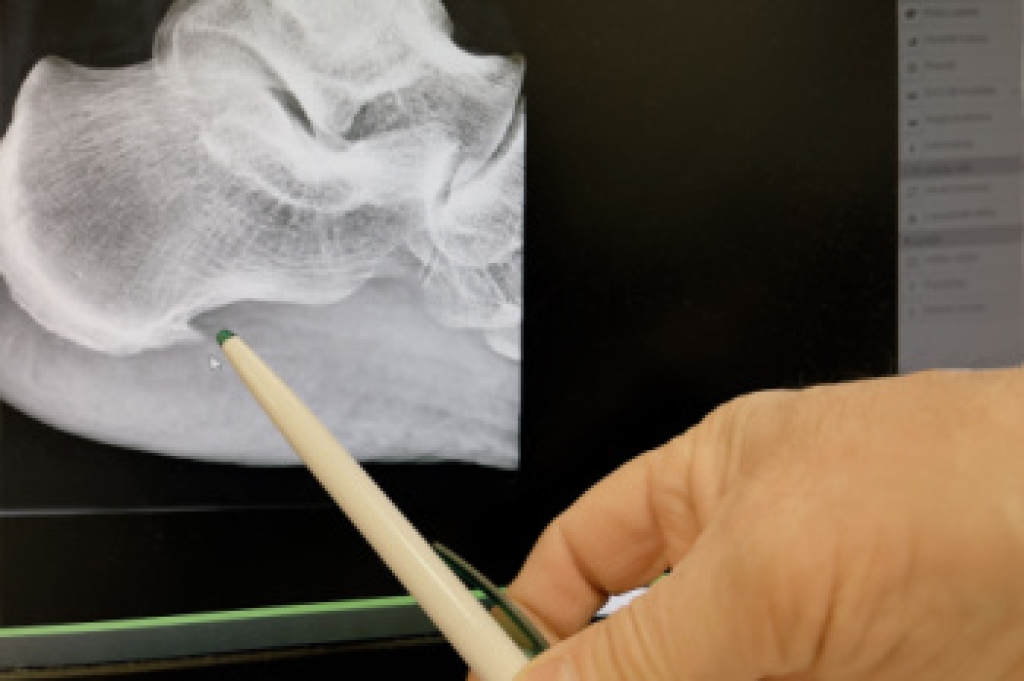

Sports related injuries are commonly treated using the RICE method. This includes rest, applying ice to the injured area, compression and elevating the ankle. More serious sprains and injuries may require surgery, which could include arthroscopic and reconstructive surgery. Rehabilitation and therapy may also be required in order to get any recovering athlete to become fully functional again. Any unusual aches and pains an athlete sustains must be evaluated by a licensed, reputable medical professional.

If you have any questions please contact our offices located in Indianapolis and Bloomington, IN . We offer the newest diagnostic and treatment technologies for all your foot and ankle needs.